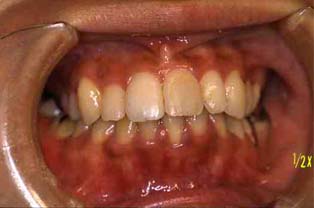

成人その3:八重歯と顎が狭い(唇側低位咬合,歯列狭窄) 22才,女性

矯正後(一年10ヶ月後)

正面

矯正治療後,歯並びもよくなって自信をとりもどした様でした。

矯正前とは違って,人前でも笑ったりおしゃべりしたりして大変明るくなりました!